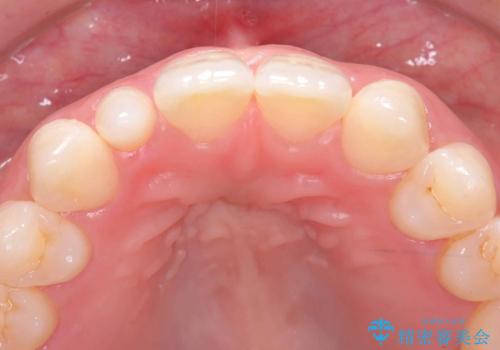

- 「前歯の見た目が気になる」を主訴に来院された患者様です。

右上2が矮小歯だったので、オールセラミッククラウンで審美修復しました。

- 税込165,000円(オールセラミッククラウンスペシャル154,000円+仮歯11,000円)費用は治療当時の料金となります